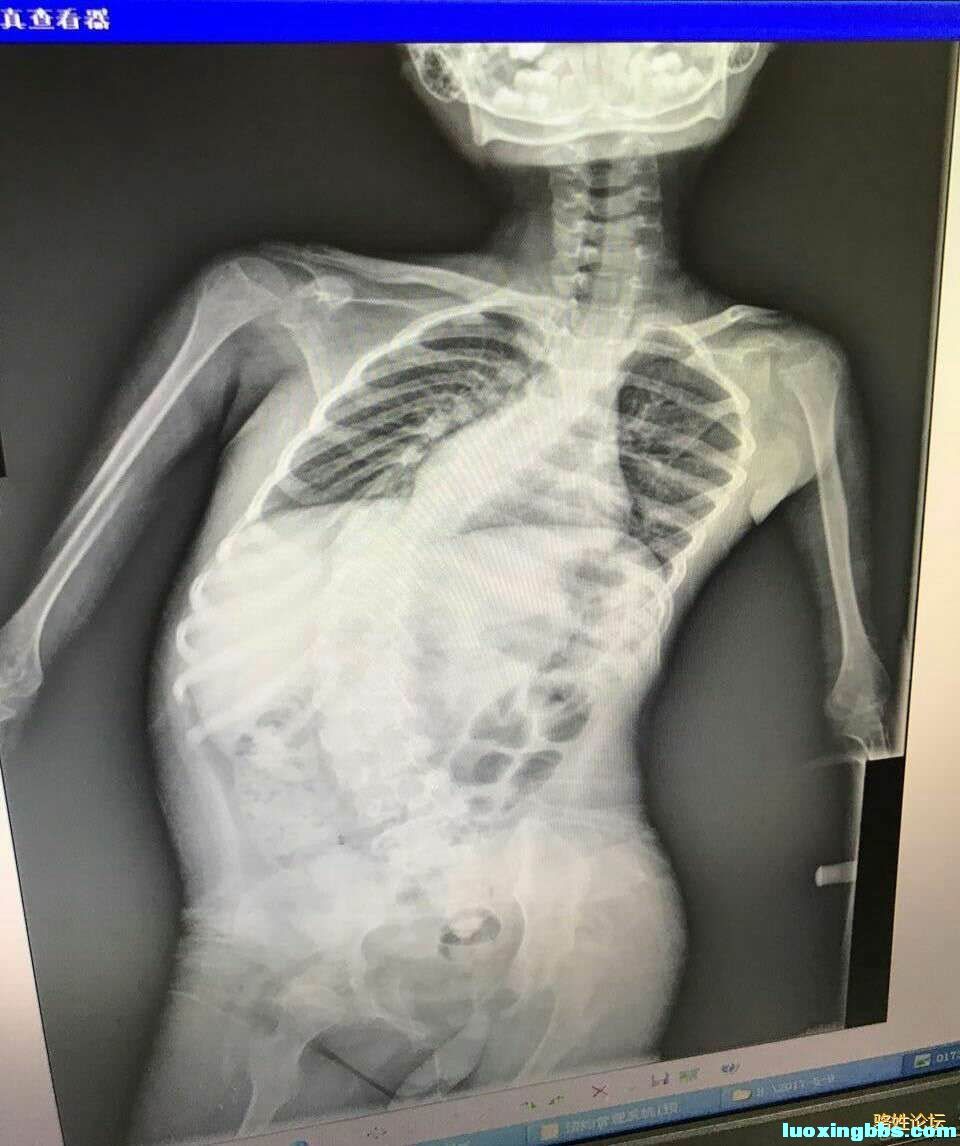

亲爱的骆氏宗親们:好!

人生要经历喜怒哀乐, 谁都想拥有健康和快乐的身体,但天有不尽人意,也有不测风云。但这病魔就降落在福建省云霄县火田镇佳园村佳栋的小诗淇身上,小诗淇脊椎不断畸形向内弯,导致内脏受影响,气管较短,连咳嗽都没有力气。医生建议尽快动手术,按现在8周岁的发育情况,如不动手术不用3年,脊柱椎的畸形生长会导致肺及其他内脏严重压迫而致命。小诗淇是骆凤娟宗親的女儿 ,骆凤娟宗親离了婚一个人带这孩子,凤娟宗親也不容易一个人打工拉扯这个孩子。

因为小诗淇住院花光了家里全部积蓄,原是不富裕的家庭,现如今已没钱冶病,全家人无计可施。

希望各位爱心人士,能够奉献一份爱心,出一份力,帮帮小诗淇吧!祝全骆氏的好心人一生平安。也祝全天下的好心人一生平安!